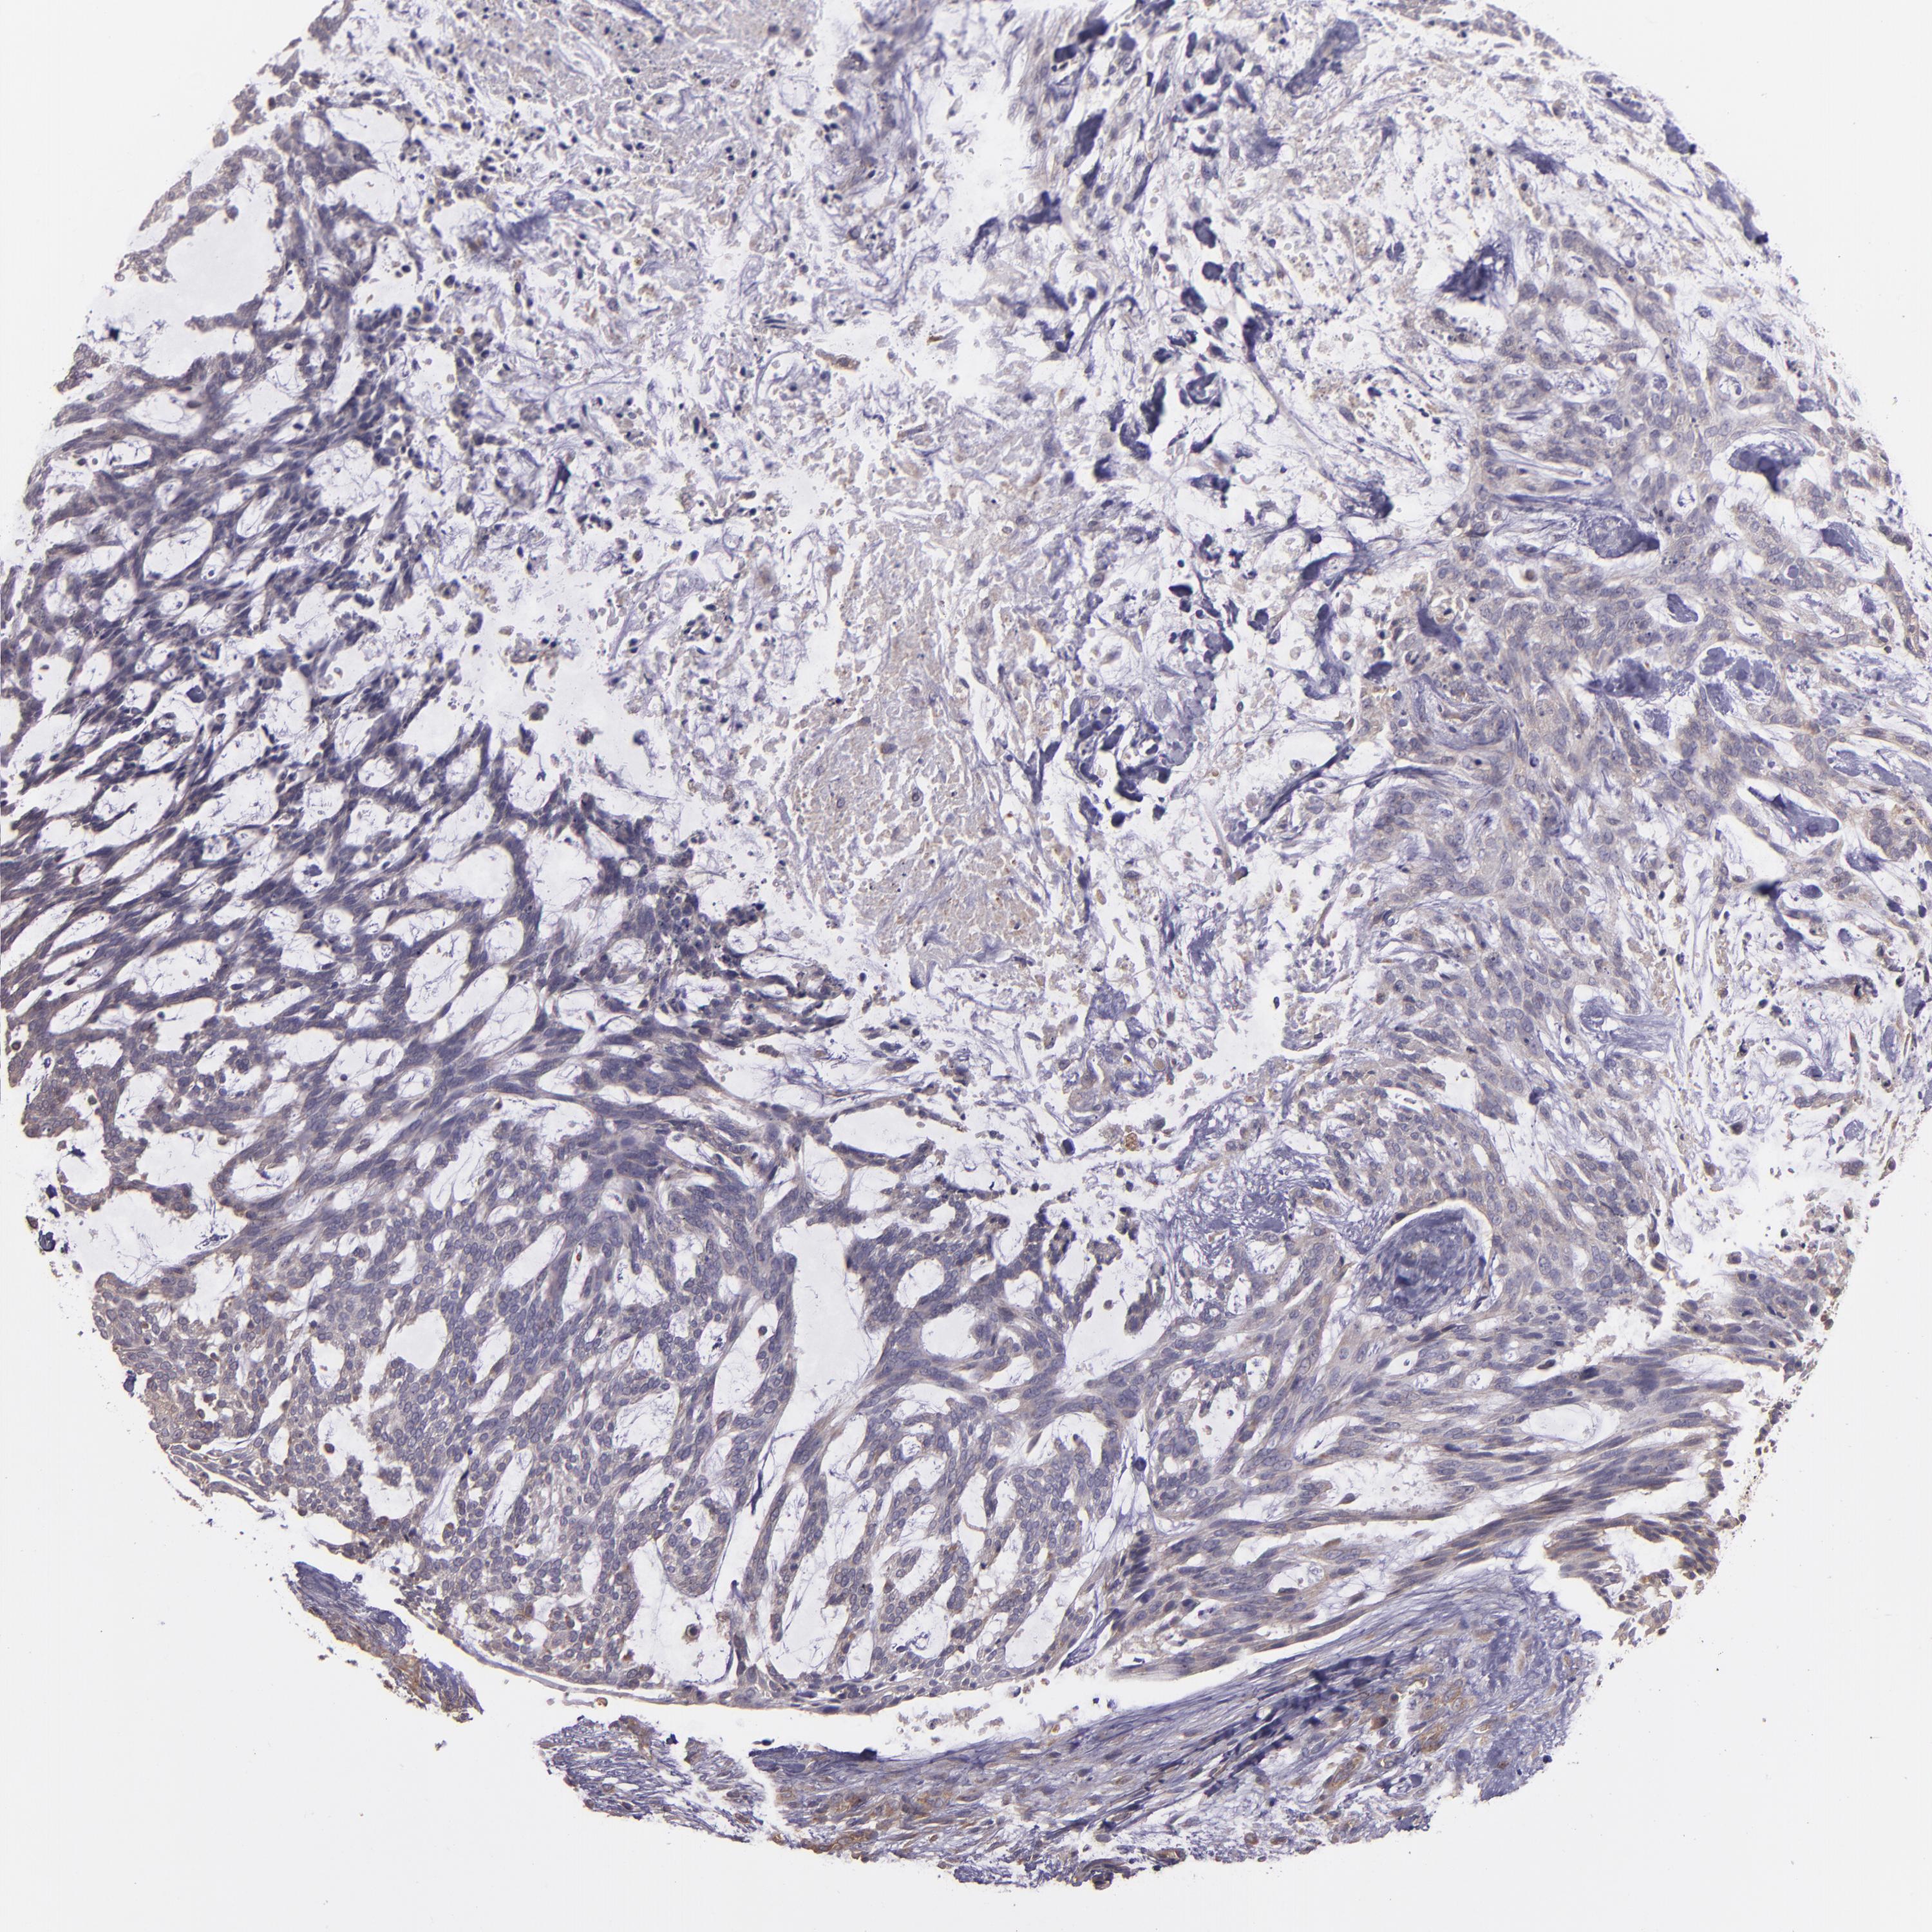

SKIN CANCER - Protein expressioni

A mouse-over function shows sample information and annotation data. Click on an image to view it in a full screen mode. Samples can be filtered based on level of antibody staining by selecting one or several of the following categories: high, medium, low and not detected. The assay and annotation is described here.

Each image is clickable and will lead to virtual microscopy that enables deeper exploration of all samples and also displays staining intensity scores, fraction scores and subcellular localization as well as patient and tissue information for each sample.

Antibody HPA013616

Basal cell carcinoma